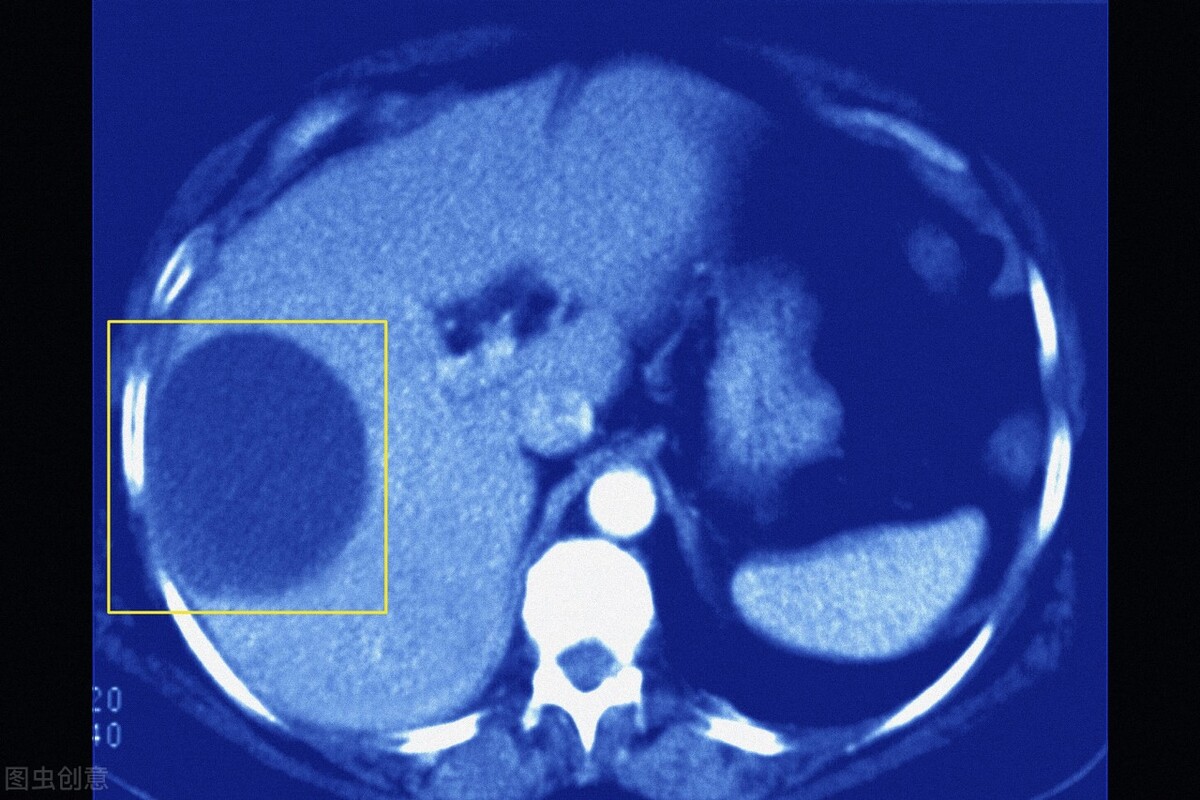

●所谓的囊肿,其实在我们临床大夫看来就是一种囊性肿物(长在肝脏的囊泡状病变)。说白了就是外层有一层囊腔包裹,中间是液体,就是这么简单,我们人体很多脏器都会有这种囊性病变,如肾囊肿、肝囊肿、卵巢囊肿等。不少人刚拿到检查报告单看到“囊肿”的字眼吓呆了,有的还以为是最近新长出来的。其实很多人都是从小就有了,因为肝囊肿中“先天性囊肿”是最常见的。

●肝囊肿是临床上常见的肝脏良性疾病,囊肿既可以是单发的,也可以是多发的,大多在肝内分散分布,大小不一,这个囊肿里面主要是清亮、无色或淡黄色液体。如果是小囊肿可长期或终生无症状。其临床表现随囊肿位置、大小、数目以及有无压迫邻近器官和有关并发症而异。如果说囊肿持续增大或者说压迫了邻近器官那就可出现餐后饱胀、食欲减退、恶心和呕吐;腹痛;腹部肿块;黄疸等表现。

●经过多年的临床实践发现,其实超声是诊断肝囊肿最简便易行的方法, 可作为肝囊肿的诊断依据, 确诊率超过95%。它已有效应用于肝囊肿的筛查, 甚至还可用于胎儿先天性肝囊肿的诊断。有大量的临床实验表明,典型的单纯性囊肿超声图像表现为内部为无回声或仅有少量低水平回声, 囊壁薄, 边缘光滑、整齐, 后壁回声增强。注意了,若囊肿合并感染或出血, 则囊内可出现弥漫性中、低水平回声, 有时底部可有分层现象, 囊壁也可增厚边缘不规则。

●虽说CT、磁共振等影像学检查方法也可显示肝囊肿的结构, 但相比之下, 其实还是超声来得更简单方便、费用低, 也容易被老百姓接受。此外, 超声对肝囊肿的敏感性也很高, 可显示肝内小至2 mm的囊肿,超声还可在对肝囊肿进行定性评价的基础上, 精确地估算囊肿的大小、形态及位置等, 从而对囊肿进行分级,故而这就是我推荐B超检查的理由。